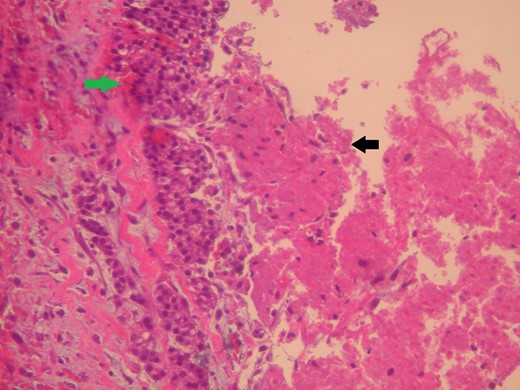

The patient was given a 7-day course of antibiotics prior to excision. The mass was then oncologically excised under local anesthesia. Histology identified infiltration of fatty abdominal wall tissue from acinic cells cancer and coagulative tumor necrosis, which led to the cystic formation of the lesion (Fig. 2). Immunohistochemistry revealed positive tumor cells for Keratin 8/18, trypsin and Chymotrypsin (Fig. 3). Further follow up scans revealed no metastasis, local recurrence or any other local growth.

The lesion (green arrow) appears cystic due to its central tumor necrosis (black arrow). Hematoxylin and eosin ×200.